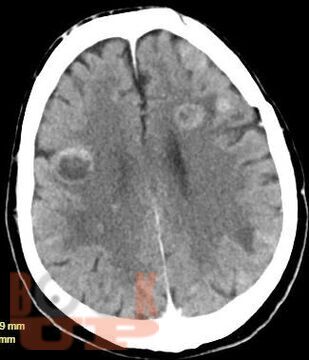

Учебное пособие освещает вопросы многоочагового поражения головного мозга. Рассматриваются различные нейрохирургические и неврологические заболевания с очагами поражения головного мозга в количестве более двух, такие как опухоли головного мозга (первичные и метастатические), воспалительные заболевания, демиелинизирующие заболевания, паразитарное поражение и другие патологии. В книге приведены алгоритмы дифференциальной диагностики данных заболеваний, начиная от особенностей клинической картины до специфики изменений сигнала в разных режимах МРТ. Также обозначена тактика ведения и прогноз заболеваний.